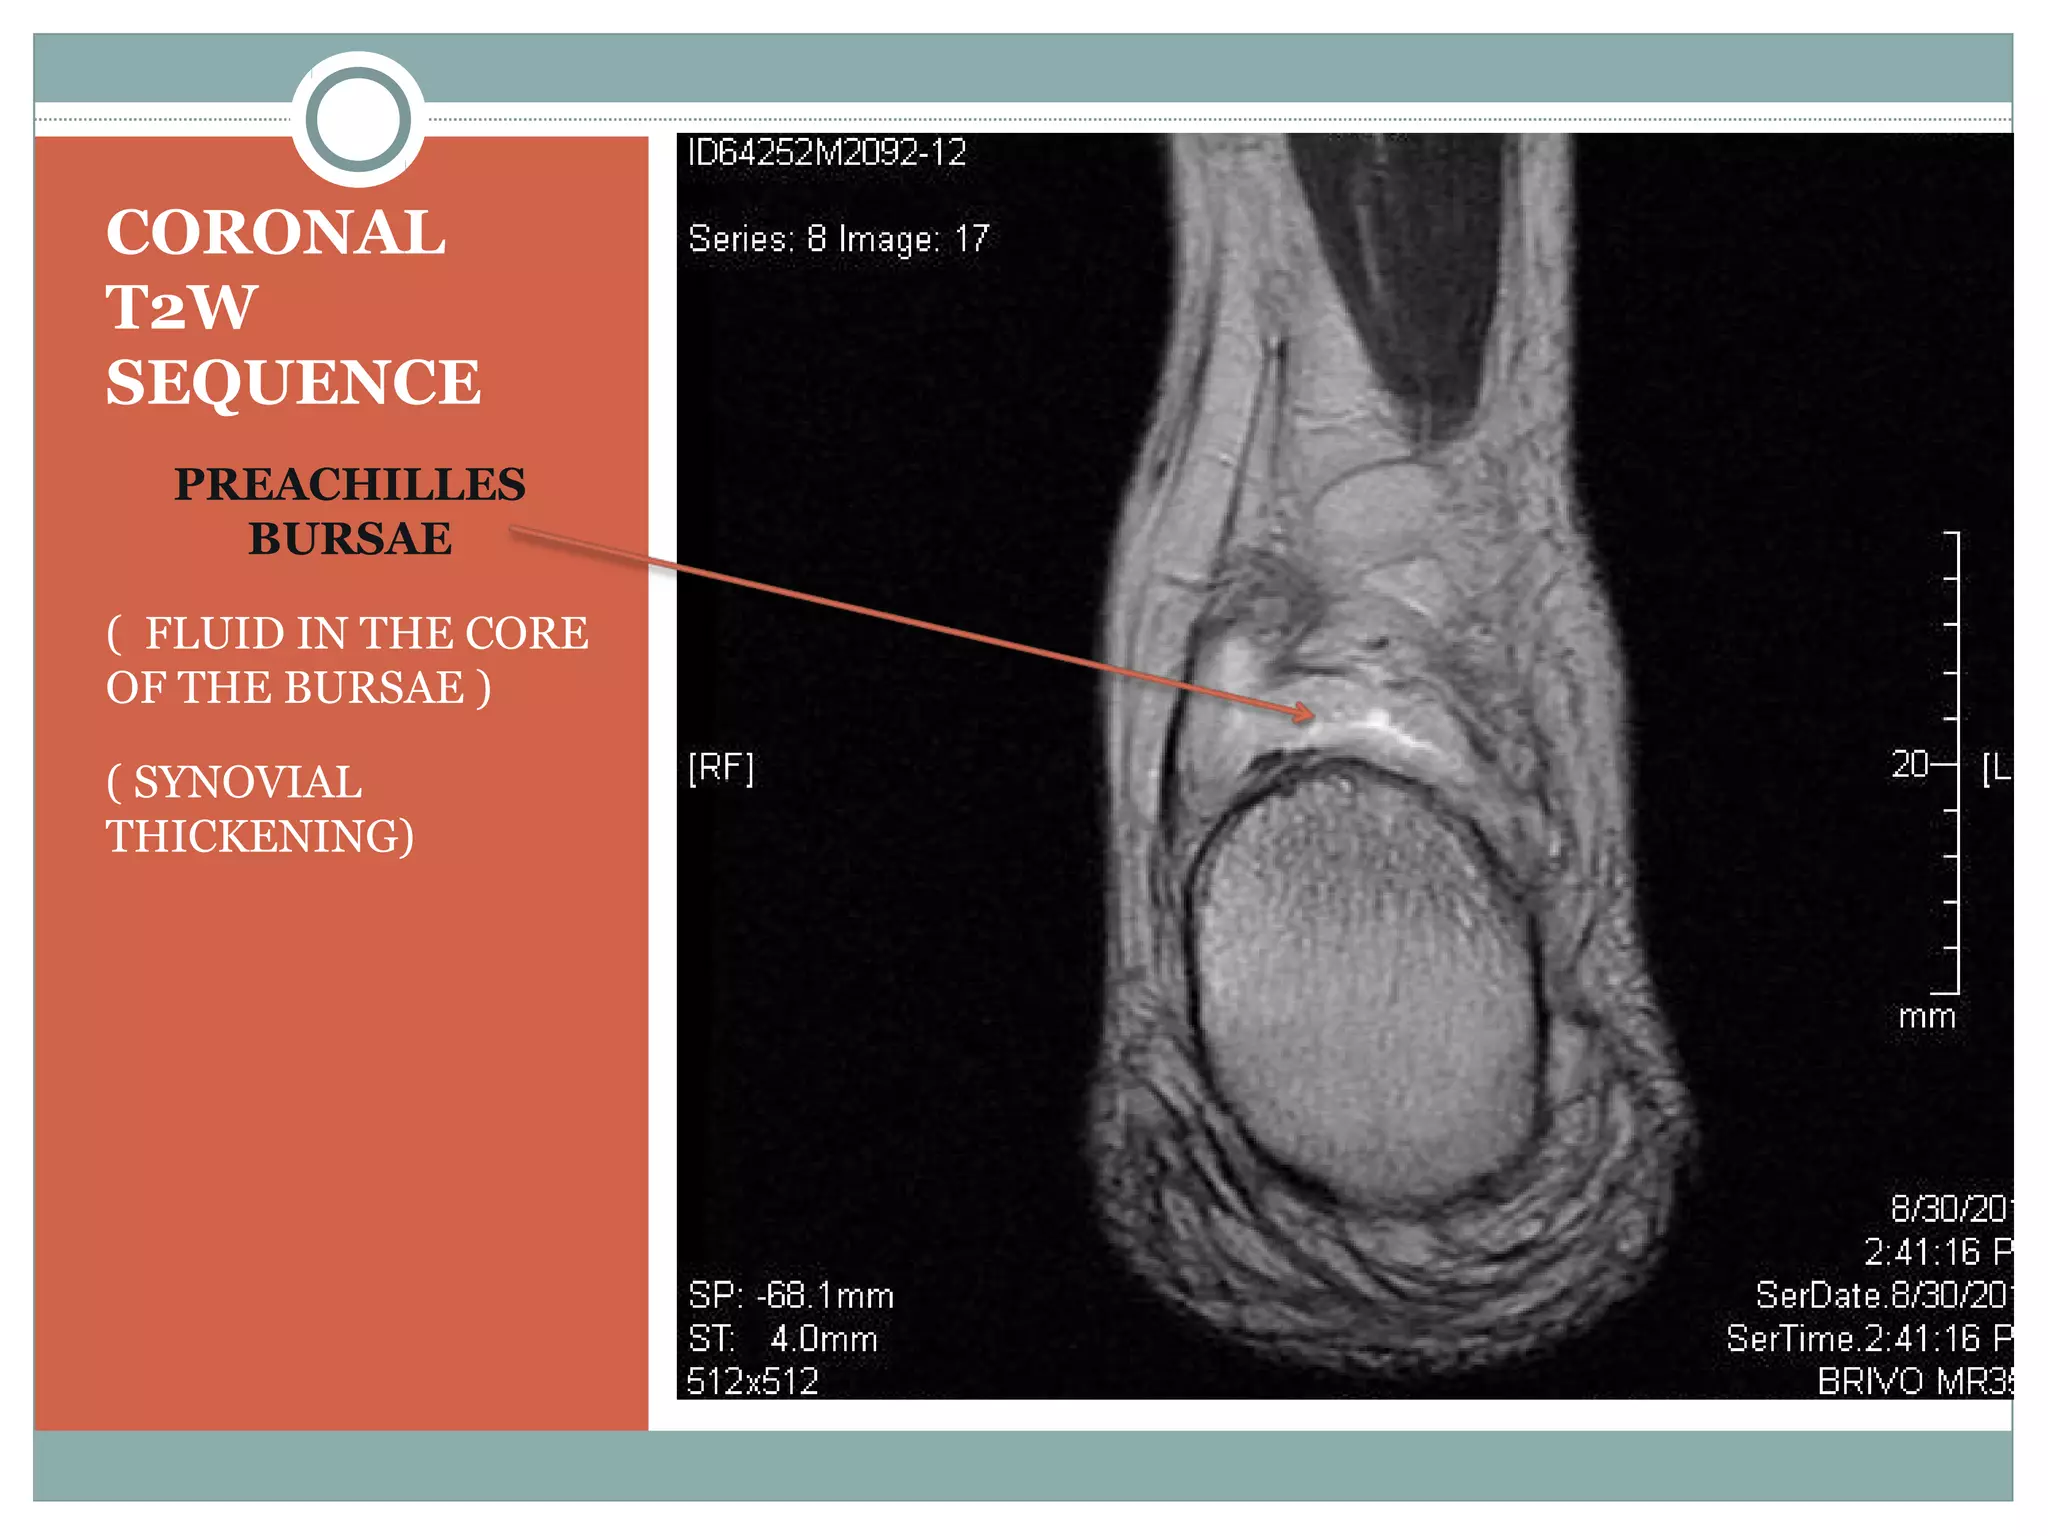

Haglunds Deformity | PPT

Haglunds deformity | PPT www.slideshare.net